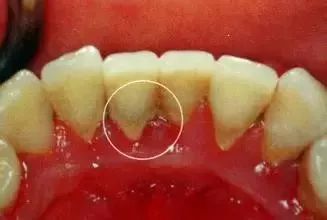

02、牙结石

牙结石是指沉积在牙面上的矿化的菌斑,根据其沉积部位和性质分为龈上牙结石和龈下牙结石两种。

(1)龈上牙结石

位于龈缘以上的牙面上,肉眼可直接看到。在牙颈部沉积较多,特别是在大涎腺导管开口相对处,如上颌磨牙的颊侧和下颌前牙的舌侧沉积更多。龈上牙石中无机盐的主要来源是唾液中的钙、磷等矿物盐。

(2)龈下牙结石

位于龈缘以下、龈袋或牙周袋内的根面上,肉眼不能直视,必须去医院检查,方能知其沉积部位和沉积量。龈下牙石中无机盐的主要来源是龈沟液。牙石对牙周组织的危害,主要是构成了菌斑附着和细菌滋生的良好环境。

半年洗一次牙及时清除牙结石

不管平时多么注意刷牙的人,牙齿上或多或少也会有牙结石。牙结石是在牙菌斑的基础上形成的一种粗糙坚硬的钙化物,多堆积在牙齿颈部。一旦出现牙结石,很容易造成牙龈出血、发炎、肿痛、溢脓甚至萎缩等。目前,清除牙结石最有效的方法就是洗牙(预防性洁治),而这也是预防牙周炎的有效方法。